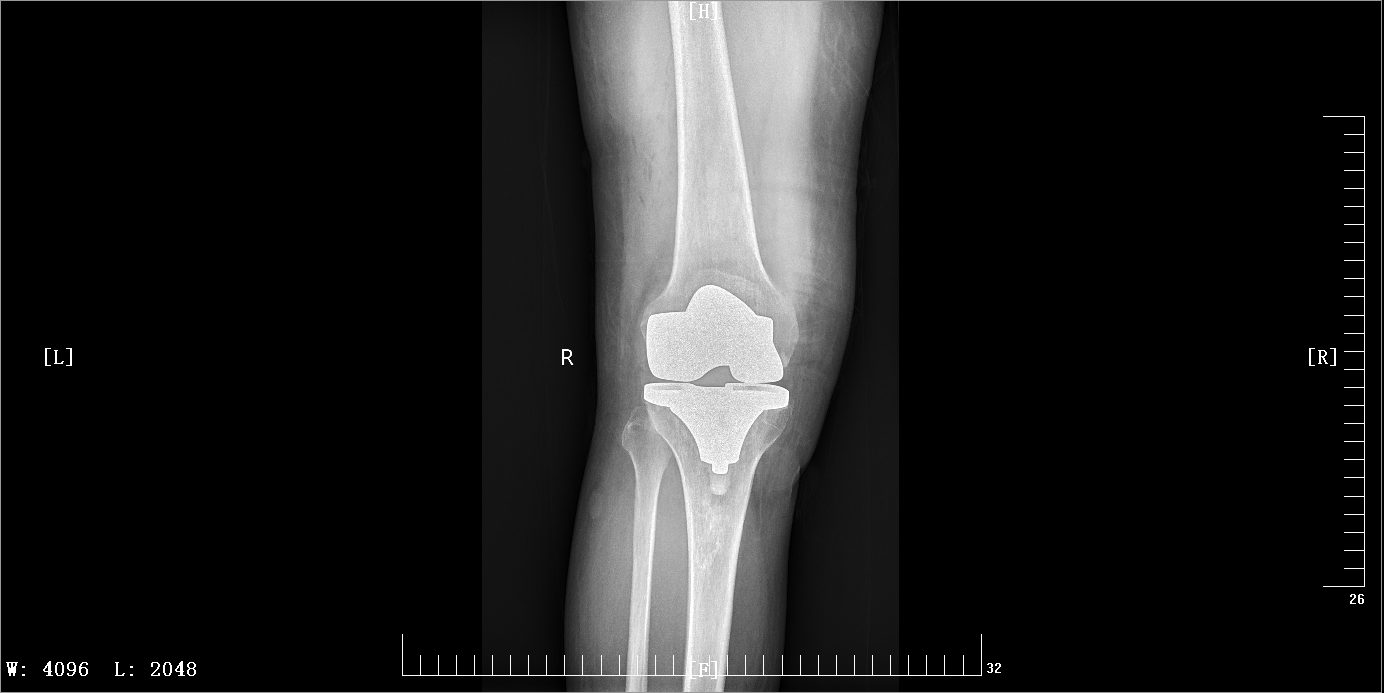

右侧膝关节术前后片

今年55岁的王某,反复出现左髋部疼痛10余年,右髋部疼痛5余年,左膝部疼痛3余年,严重影响生活质量。于11月30日到广安区人民医院就诊,经CT诊断为:双侧股骨头缺血性坏死、双膝关节骨性关节炎。遂到医院骨二病区办理入院治疗。12月4日,医院骨科关节团队分次为患者进行双侧髋关节、双侧膝关节置换手术,术后完全康复,患者十分满意。

膝关节骨性关节炎是指由于膝关节软骨变性、骨质增生而引起的一种慢性骨关节疾患,又称为膝关节增生性关节炎、退行性关节炎及骨性关节病等。本病多发生于中老年人,也可发生于青年人;可单侧发病,也可双侧发病。严重者导致关节残疾、影响患者生活质量。